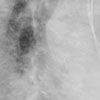

An ECG revealed a ventricular paced rhythm with right bundle-branch block (BBB) morphology and extreme axis deviation (A). The anteroposterior (AP) chest radiograph showed normal placement of the electrodes (B); however, the lateral film revealed a posterior deflection with the ventricular electrode entering the coronary sinus and resting in a contributory branch (C).

The differential diagnosis of paced right BBB morphology includes inadvertent LV lead placement, migration of the electrode into the LV (through a patent foramen ovale, atrial septal defect, or septal perforation), inadvertent coronary venous system placement, or right bundle-branch disease with anterograde block. Right BBB morphology during pacing requires further studies to determine the cause. As demonstrated in this case, the lat-eral chest radiograph is an essential part of the routine postoperative follow-up of patients with pacemakers. However, both AP and lateral films may be normal in patients with inadvertent coronary sinus lead placement.1 Echocardiography, which may be impractical, and intracardiac ECG, which is ideally performed in the electrophysiology laboratory immediately after implantation, also can be used to confirm correct electrode placement.